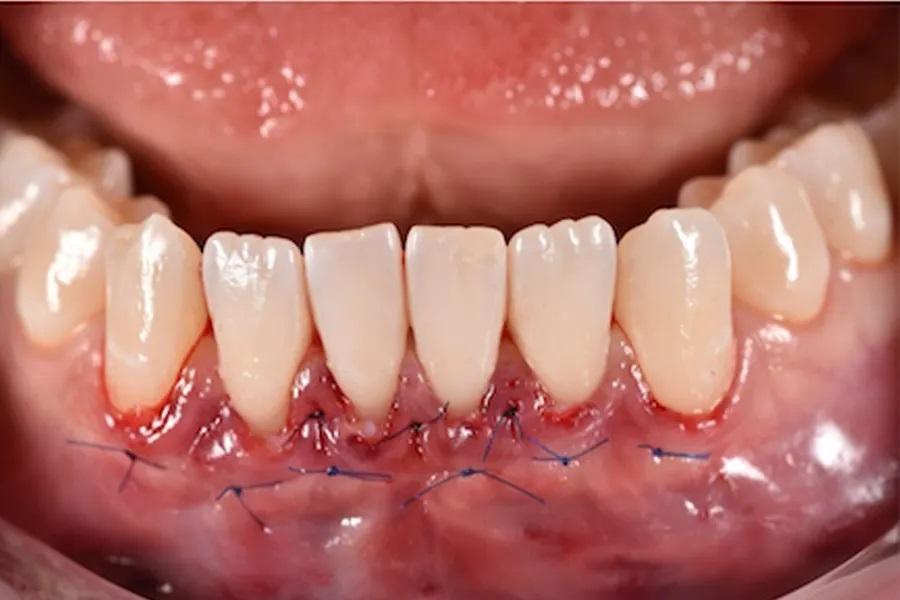

При тонком фенотипе с начальными рецессиями минимально инвазивная тоннельная техника с применением СТТ (при необходимости — с использованием эмалевых матриксных белков на оголенных корнях) позволяет увеличить толщину мягких тканей и обеспечить долгосрочную стабильность после ортодонтического перемещения зубов. (фото 13 – 16)

Фото 13. Закрытие рецессии с использованием СТТ, выполненное методом тоннелирования. Реципиентные участки были подготовлены с применением минимально инвазивной тоннельной техники с краевым разрезом без вертикальных релизных разрезов. Тоннель был расширен в межзубных промежутках для атравматичного введения трансплантата при сохранении целостности сосочков и оптимального кровоснабжения со стороны слизисто-надкостничного лоскута.

Фото 14. Фиксация СТТ с помощью подвешивающих швов, проведенных через межзубные сосочки. Швы фиксировались к неподвижной язычной/небной десне, обеспечивая стабильное корональное смещение без натяжения краевых тканей.

Фото 15. Подвешивающие швы, техника двойной фиксации. Использовались тонкие монофиламентные шовные материалы для точной адаптации трансплантата и краев лоскута. Такой подход обеспечивал пассивное положение тканей, минимизировал микроподвижность трансплантата и способствовал предсказуемой реваскуляризации. Швы были сняты через 10 дней.

Фото 16. Результат закрытия рецессии с использованием СТТ через 12 недель после операции. Отмечается полное закрытие корней и значительное утолщение мягких тканей. Муко-гингивальная линия стабильна, цвет и текстура тканей гармоничны. Трансплантат успешно интегрировался, сформировав здоровый и эстетичный краевой контур, соответствующий долгосрочной пародонтальной стабильности.